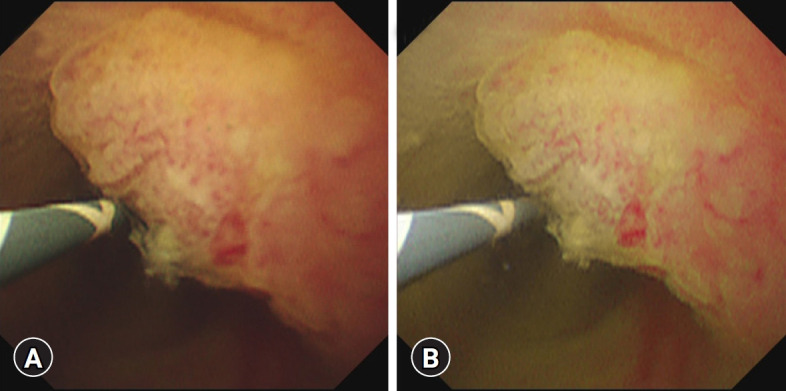

Endoscopic retrograde cholangiopancreatography (ERCP) is the gold standard for the evaluation of biliary strictures and the management of bile duct stones. However, standard ERCP techniques sometimes fail for both indications. In such situations, peroral cholangioscopy (POCS), which allows direct visualization of the bile duct, can play a significant role in diagnosis and treatment. Direct visualization using POCS can help differentiate between malignant and benign conditions and is more accurate in defining the extent of cholangiocarcinoma. Furthermore, POCS enables visually guided biopsies. Certain types of difficult bile duct stones, such as impacted and intrahepatic stones, require POCS for visually guided lithotripsy. Recent advancements in POCS will broaden its applicability and improve its diagnostic utility. In this review, we provide perspectives on the past, present, and future of POCS.